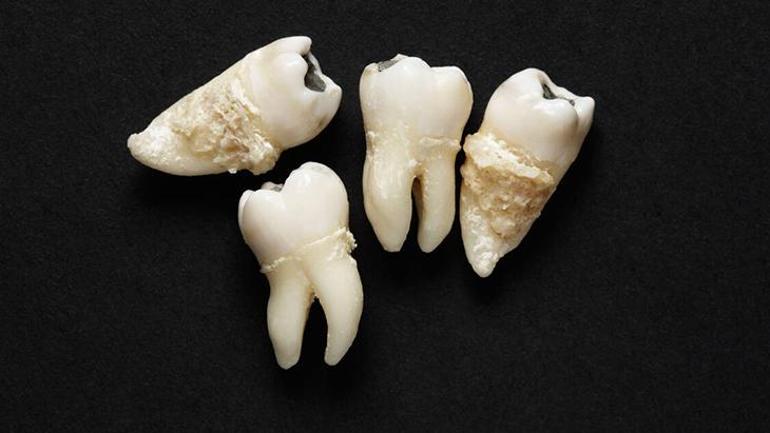

2000’li yıllarda uzmanların radarına takılan 20’lik dişin birçok sıhhat meselesine deva olabileceği fikri yıllar içinde geliştirilerek araştırmalarla birlikte son nokta kondu. Günümüzde pek çok kişi için gereksiz kabul edilen yirmilik dişin kök hücrelerinin beyin hücrelerinden kıkırdağa kadar farklı insan dokularına dönüşebildiği ortaya çıktı. Yirmilik dişlerin pulpa kısmının, mezenkimal kök hücreler açısından varlıklı olabileceğini gösteren bu çalışmalar sayesinde artık kimi diş klinikleri, çekilen 20’lik dişlerden kök hücre toplamaya ve bunları özel biyobankalarda saklamaya başladı. ABD ve Avrupa’da yirmilik dişler artık çöpe atılmıyor, biyobankalara gönderiliyor. Tıbbi bir hazine olarak nitelendirilen yirmilik diş hangi hastalıklara potansiyel bir tedavi sunuyor? Tüm ayrıntıları Ağız, Diş ve Çene cerrahisi Uzmanı Doç. Dr. Münir Demirel’e sorduk.

Açıklamalarına yirmilik dişlerin saklanmasının gelecekteki potansiyel tedaviler açısından kıymetli bir biyolojik kaynak sağlayabileceğini söyleyerek başlayan Doç. Dr. Münir Demirel, “Bu dişlerin pulpa dokusu, mezenkimal kök hücreler (MSC) açısından zengindir. MSC’ler, hudut, kas, kıkırdak, kemik ve yağ hücrelerine farklılaşma kapasitesine sahiptir. Kök hücre bankacılığı alanındaki gelişmelerle birlikte, bilhassa 20’lik diş üzere doğal kaynakların korunması, bireye özel rejeneratif tedavi seçenekleri sunma potansiyeline sahiptir” dedi.